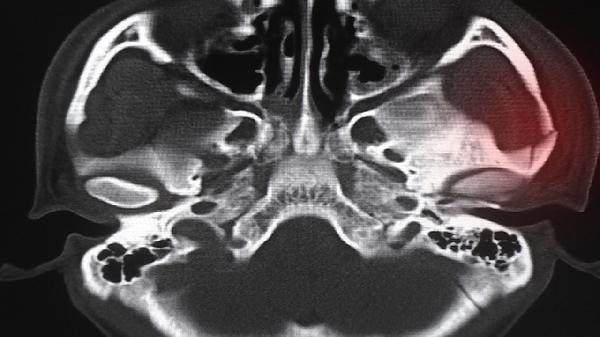

儿童可能出现方颅、肋骨串珠等佝偻病样改变,成人常见脊柱后凸、骨盆狭窄等畸形。畸形与长期负重状态下未矿化类骨质变形有关,严重时可能影响呼吸功能。需使用大剂量维生素D2软胶囊进行冲击治疗,必要时进行矫形手术干预。